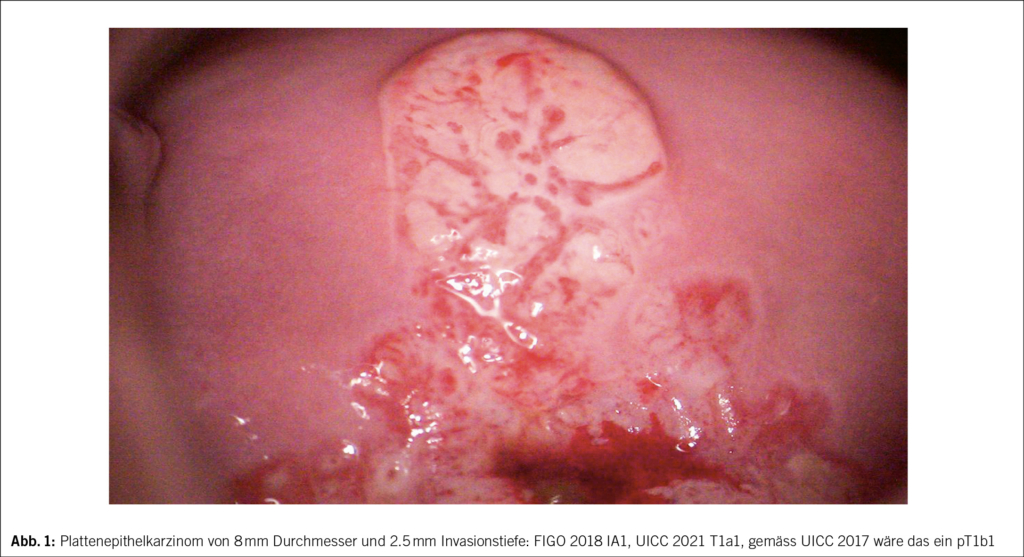

Die FIGO 2018 und UICC 2021 Klassifikation berücksichtigt die oberflächliche Ausdehnung eines frühen Karzinoms nicht mehr und klassifiziert allein aufgrund der Invasionstiefe: IA1 mit < 3 mm Invasionstiefe, IA2 mit 3.1– < 5 mm, IB1 > 5 mm Invasionstiefe und unter 2 cm Tumordurchmesser etc.